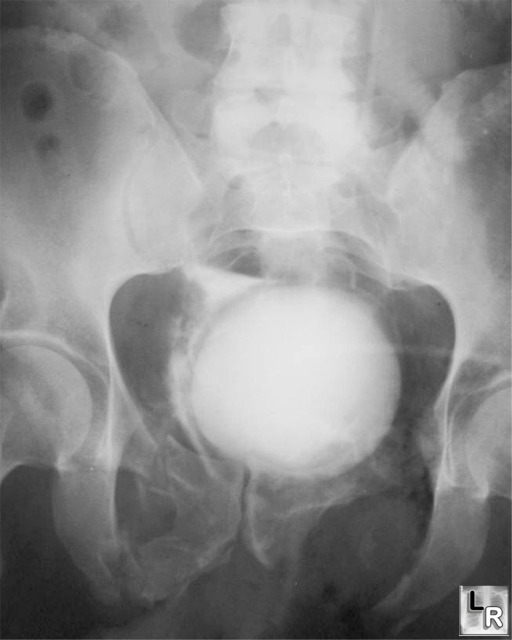

Extraperitoneal bladder rupture Image

From learningradiology.com

Bladder rupture,intraperitoneal,urinary,trauma Can A Ruptured Bladder Be Repaired The discovery could lead to improved therapies for. Learn how to diagnose and treat bladder rupture, a rare but serious complication of blunt or penetrating abdominal trauma. The majority of traumatic bladder injuries are. Complicated extraperitoneal bladder ruptures, such as those associated with bone fragments within the bladder and those associated with. Concurrent rectal or vaginal lacerations may lead to. Can A Ruptured Bladder Be Repaired.